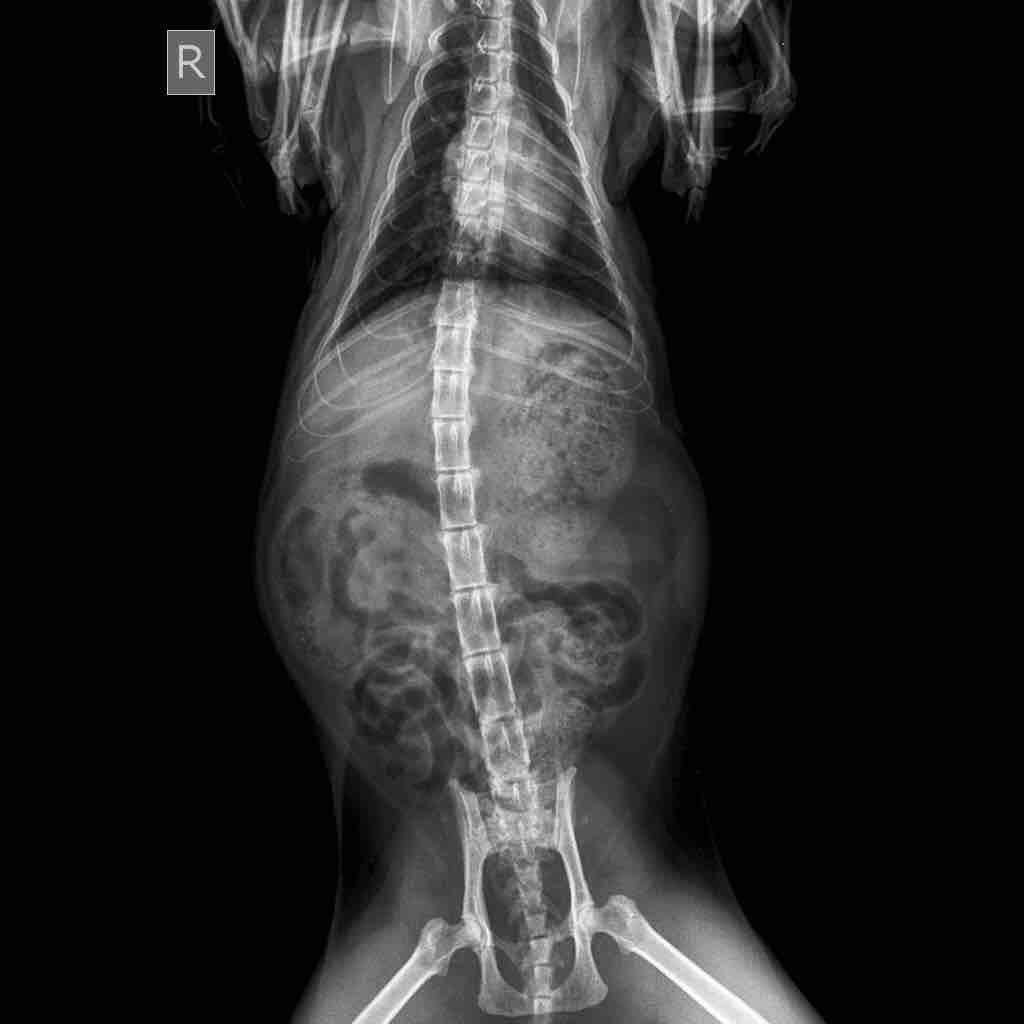

Took biscuit to the vet today and after taking an x-ray we found out that her bladder was full and that there are stones in the bladder. The vet isn’t very optimistic as he said a surgery would only be a temporary solution and that it’s the tendency of her body to create these stones, also there might be complications during the surgery. I have come to you for a second opinion. Please help me.